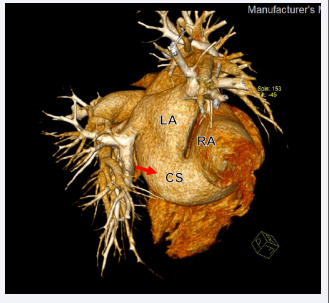

A 25-year-old young female with no history of medical illness had recently developed flu symptoms and had an ejection systolic murmur on auscultation. During her childhood, she had no dyspnea or palpitations. As part of her evaluation, she had a chest X-ray, which revealed cardiomegaly. She then had a TTE, which revealed dilated atria, right ventricle, and an interatrial shunt. As a result, she was referred to our facility for further evaluation. She had a loud left parasternal systolic murmur at the second intercostal space on auscultation. Her saturation level was 98%. ECG showed a sinus rhythm with right axis deviation and complete RBBB. Repeat TTE at our facility confirmed that her right atrium (RA) and right ventricle (RV) are dilated with RV mid-diameter of 51 mm (Figure 1,2),

Figure 1: Two-dimensional TTE, apical 4-chamber view, systolic phase, demonstrates a dilated RA. RA, Right Atrium: LA, Left Atrium: RV, Right Ventricle: LV, Left Ventricle.

Two-dimensional TTE, apical 4-chamber view, diastolic phase,  demonstrates a dilated RV with a mid-segment diameter of 51 mm.

Figure 2: Two-dimensional TTE, apical 4-chamber view, diastolic phase, demonstrates a dilated RV with a mid-segment diameter of 51 mm.